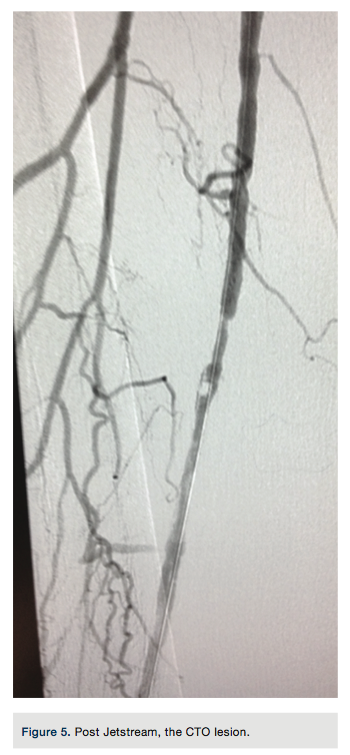

to gain purchase in the distal vessel within the true lumen. Placement was confirmed with a hand injection angiogram into the popliteal artery. There was no evidence of dissection. Routine debulking atherectomy was performed with the Jetstream Navitus 2.4 to 0.4 mm device with blades down (Figure 3) and blades up across the occluded segment (Figures 4-5) over the Spartacore wire. Balloon dilation was then performed with 5.0 x 80 mm and 6.0 x 80 mm Chocolate balloons (Trieme Medical)

(Figure6). There was an excellent angiographic result (Figure 7). The final angiographic image showed a -10% residual stenosis and brisk flow distally, with no dissection or extravasation of contrast. A pullback gradient assessment of femoral and popliteal artery to the proximal right SFA was performed and no gradient found. The Pinnacle Destination sheath was removed and a Perclose (Abbott Vascular) technique was used for left common femoral artery vascular access closure.